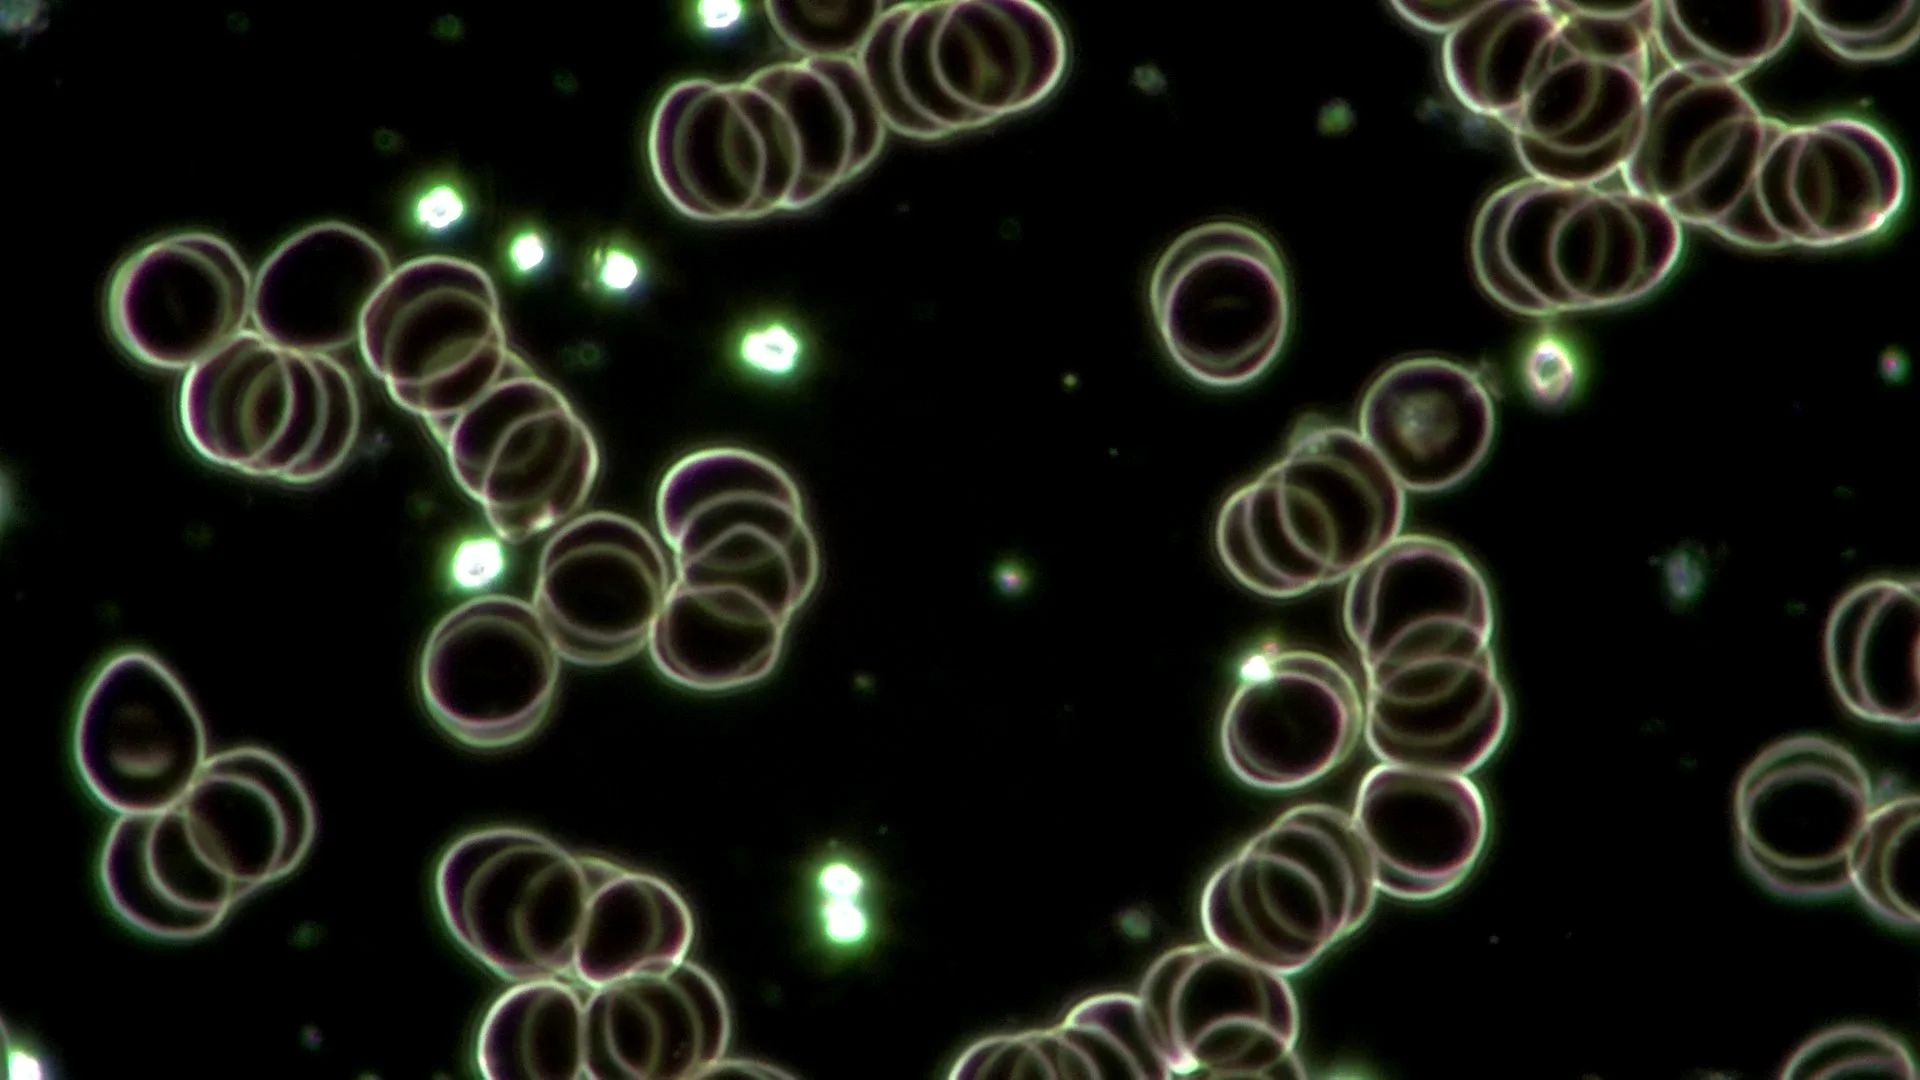

In just 15 minutes of conscious breathing, her blood went from stressed and disease-prone to healthy and healing

The live blood cell image reflects the stress her emotional state was having on her physiology. These cells stack together as ‘coins.’ This indicates there is inflammation, dehydration and possibly an acidic cellular environment. Long-term, this can lead to physical health imbalances and chronic diseases.